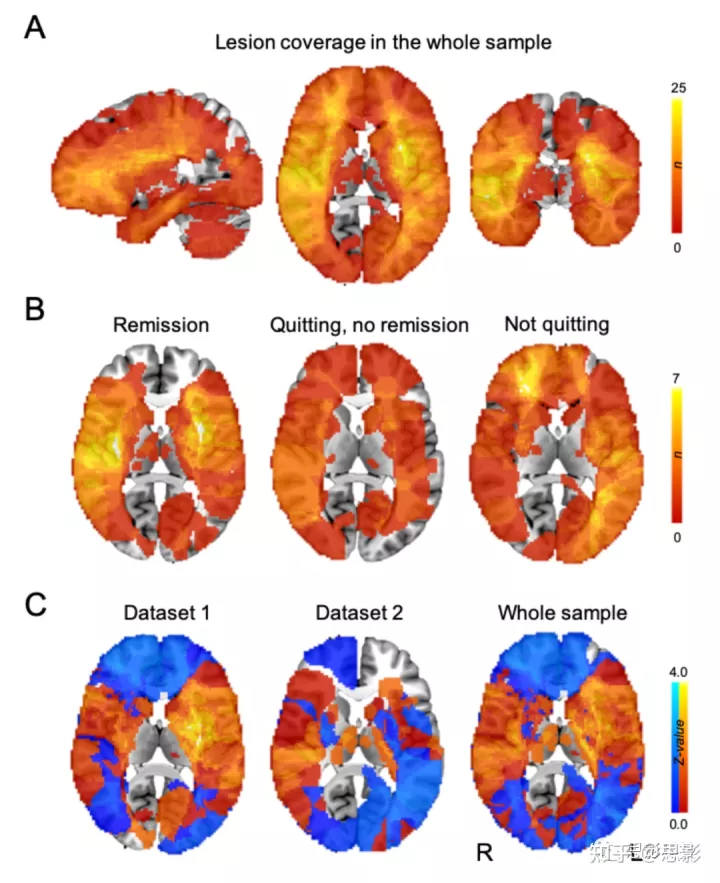

图 S2:病变位置和体素-病变症状映射(voxel-lesion symptom mapping, VLSM)结果。

在我们的两个队列(n = 129)中结合每天活跃吸烟者的病变位置,并叠加生成所有病变(A)或与特定临床结果相关的病变(B)的病变覆盖图。体素强度反映了与每个脑体素相交的病变数量。构建 VLSM z-map 以识别爱荷华数据集(C,左)、罗切斯特数据集(C,中)和两个数据集(C,右)的成瘾缓解最相关的体素。暖色表示成瘾缓解组中的体素更可能受损,而冷色表示非戒烟者中的体素更可能受损。使用爱荷华州(C,左)和罗切斯特(C,中间)队列构建的成瘾缓解 VLSM z-map 与预期相似。由于没有与成瘾缓解显著相关的体素,VLSM 地图显示为未阈值。

鉴于这种病变位置的异质性,我们接下来测试了破坏成瘾的病变位置是否映射到连接的大脑回路而不是一个特定的大脑区域。比较了导致吸烟成瘾缓解的病变位置和非戒烟者的病变位置之间的连接模式(图2a和图2b)。与我们对病变位置的阴性分析相反,我们发现了病变连接性的多个显著差异(FWE P, family-wise error-corrected P (PFWE<0.05)); 图2c和图2d)。该结果与我们是否使用来自活跃的日常吸烟者的连接组或大型规范连接组无关。我们将这张地图称为我们的成瘾缓解网络。该图中的正性区域显示出与破坏吸烟成瘾的病变位置更强的正功能连接(与非戒烟者的病变位置相比)。同样,负性区域与破坏吸烟成瘾的病变位置显示出更强的负功能连接(与非戒烟者的病变位置相比)(图2c-图2f)。因此,可能导致成瘾缓解的病变将与扣带回和脑岛呈正相关,但与内侧前额叶皮层呈负相关。相反,具有相反连接特征的病变最不可能导致成瘾缓解。

图2:成瘾缓解的LNM。

a,使用VLSM比较与吸烟成瘾缓解(左,红色显示的单个示例)和不戒烟(中间,红色显示的单个示例)相关的病变位置,但没有显著发现(右)。 b,接下来,使用LNM计算功能连接到每个病变位置的大脑区域网络。从a中显示了相同的两个病变示例的网络图。正功能连接值以暖色显示,负功能连接值以冷色显示。对病变网络图进行统计学比较,以确定与吸烟成瘾缓解显著相关的连接(右,b)。c-e,破坏成瘾的病变位置显示了使用吸烟者(c)或规范连接组(d,e)计算的大脑连接的特定模式。所有后续分析中使用的规范连接组导出的地图显示在脑切片(d,e)和脑表面(f)上。这种模式包括与岛叶、背扣带和背外侧前额叶皮层的正连接性,以及与内侧前额叶和颞叶皮层的负连接(补充表2)。c,d, 使用FSL中默认参数的无阈值聚类增强功能(单侧PFWE< 0.05)。e,f,非阈值化地图,以更好地说明纹状体(e)和额叶皮层(f)的背侧/腹侧解离。

我们的成瘾缓解网络在纹状体中显示出惊人的解离,在背侧与腹侧纹状体的边界处从正性变为负性(纹状体区域×病变组相互作用 F (1,101)=8.4, P=0.005)(见图2e)。这种分离反映在前额叶皮层,背外侧前额叶皮层呈正连接,腹内侧前额叶皮层呈负连接(见图2f)。